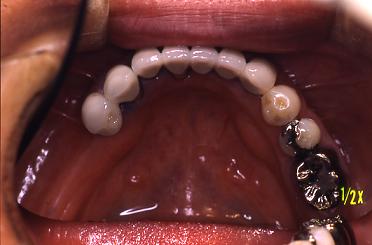

インプラントを4本植めました

(術直後)